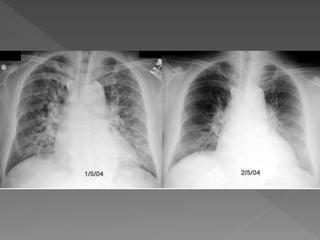

• Chest x-ray –cardiac size and state of

pulmonary vasculature .